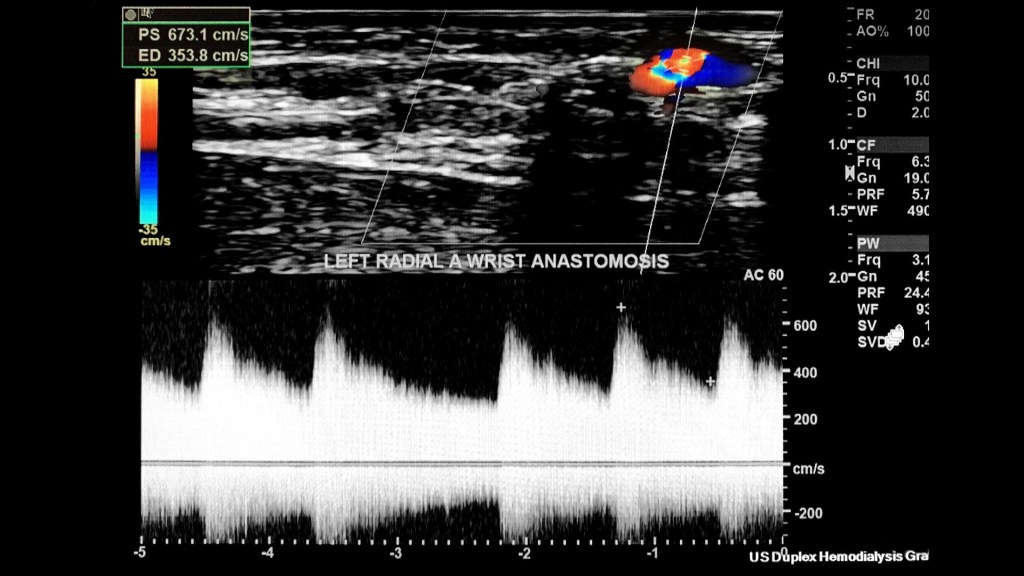

This patient has a left arm radial-cephalic vein AV anastomosis (aka Brescia-Cimino) which is the most common AVF connection.

Evaluate the patency and maturity of the fistula while also monitoring the inflow/outflow streams as well as assessing the site of anastomosis.

In this case the radial artery is the inflow; and the forearm cephalic vein the outflow.

I sampled the arterial anastomosis side a few times with the highest PSV/EDV as 673/354 cm/s.

Make sure to measure the size of the anastomosis before completing the exam.

This case proved the fistula was patent and optimally matured.